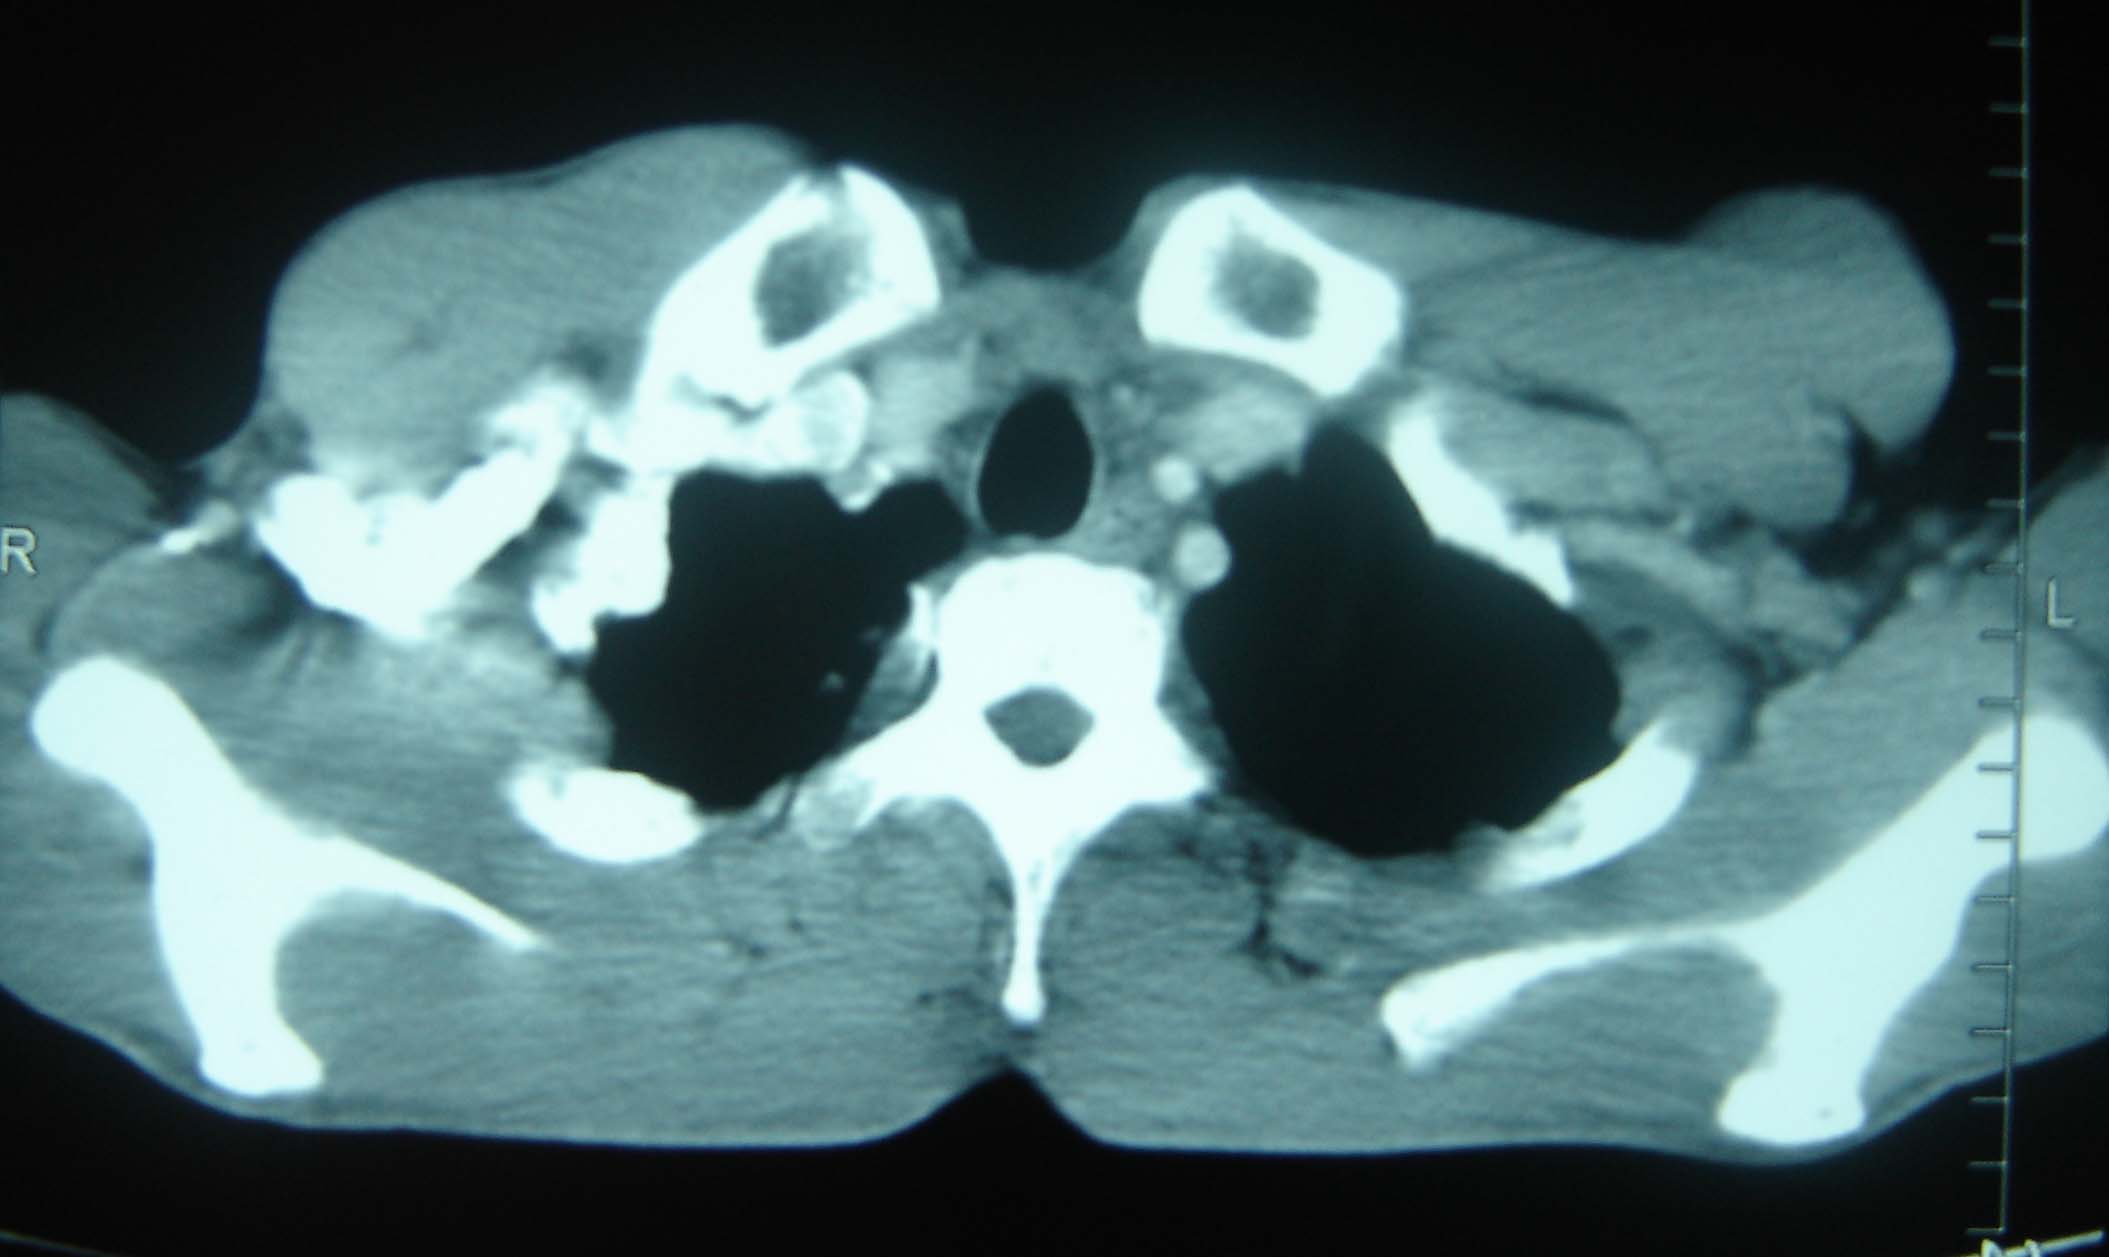

标题: CT25321:两肺多发结节 请会诊 [打印本页]

标题: CT25321:两肺多发结节 请会诊

男 、43岁,咳嗽胸痛,装修工,平时接触粉尘较多,有吸烟史10多年,纤维支气管镜检查未发现异常,胃镜、腹部b超检查亦未发现异常,颈部淋巴结活检未发现肿瘤细胞。

结节病?转移瘤?

1)考虑双肺及胸膜多发性转移瘤。2)肺气肿。

双肺结节病。